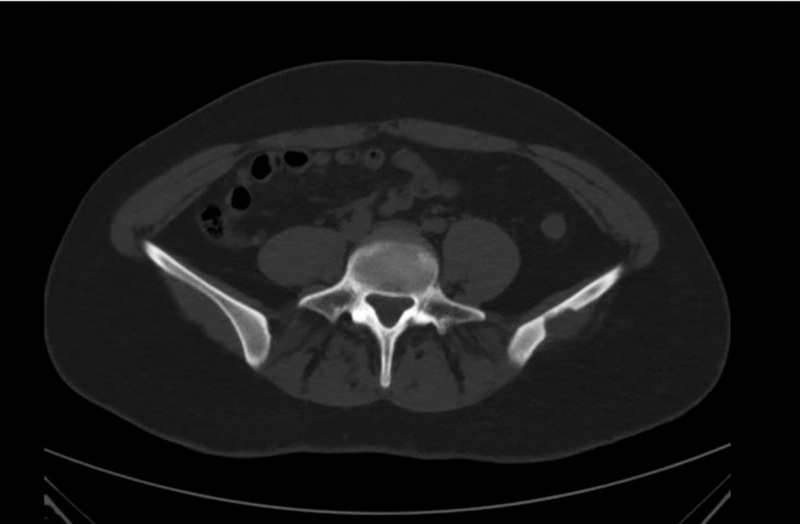

Два случая верифицированной солитарной эозинофильной гранулёмы: визуализация методами КТ, МРТ и 18F-ФДГ ПЭТ/КТ

В работе представлены два клинических наблюдения эозинофильной гранулёмы кости, диагностированной методами компьютерной, магнитно-резонансной и позитронно-эмиссионной томографии с 18F-фтордезоксиглюкозой, совмещённой с компьютерной томографией. В обоих случаях пациенты поступили в клинику с подозрением на первичную злокачественную опухоль кости, по результатам комплексного лучевого диагностического исследования и гистологической верификации установлен диагноз солитарной эозинофильной гранулёмы. Солитарная эозинофильная гранулёма кости ― достаточно редкое (менее 1% случаев всех опухолевых объёмных образований скелета) заболевание. Наиболее часто эозинофильная гранулёма обнаруживается в теменной и лобных костях черепа и представляет собой остеолитическое объёмное образование, постепенно увеличивающееся в размерах. Несмотря на то, что бΌльшую часть опухолей костной ткани можно выявить при помощи рентгенографии, предпочтительно применение компьютерной томографии, в первую очередь из-за её превосходной способности визуализировать деструкции кортикального слоя кости. Диагностическая точность компьютерной и магнитно-резонансной томографии может быть различна. Комплексное применение методов лучевой и радионуклидной диагностики позволяет сузить спектр дифференциального диагноза. К сожалению, относительно низкая специфичность существующих лучевых диагностических исследований в большинстве случаев не позволяет установить точный диагноз, и методом выбора остаётся биопсия с последующим патоморфологическим исследованием. Данные клинические наблюдения показывают необходимость включения эозинофильной гранулёмы в дифференциальный диагноз при обнаружении солитарного остеолитического очага.